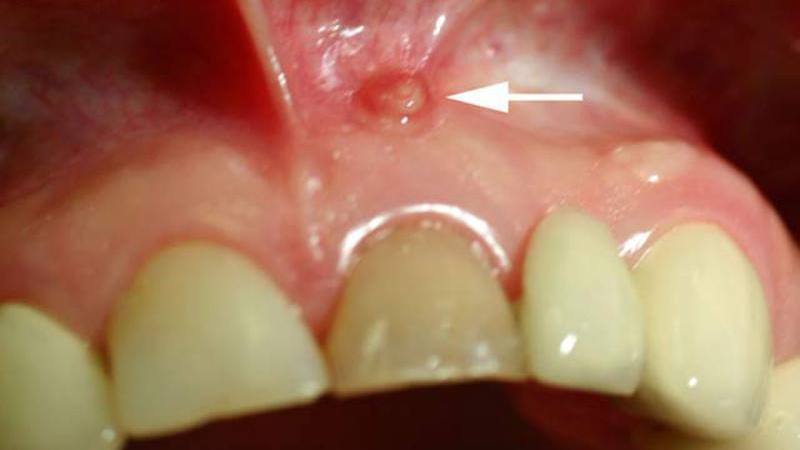

Большинство из этих образований могут долгое время оставаться незамеченными и безболезненными. Однако, достигнув определенных размеров, они могут проявляться в виде выпуклого округлого образования с истончением стенки челюсти.

Симптоматика зависит от характера воспалительного процесса. При хронической форме наблюдаются дискомфортные ощущения в зубе, особенно при употреблении твердой пищи. В некоторых случаях может происходить смещение зубов и их потемнение. Рост кисты усиливается, когда организм ослаблен в борьбе с инфекцией, что приводит к воспалению с образованием гнойных масс. В результате зуб начинает болеть, появляется выраженная отечность и свищи. У пациентов могут возникать головные боли, общее недомогание, слабость, повышенная температура и увеличение лимфатических узлов. В таких случаях крайне важно незамедлительно обратиться к специалистам.